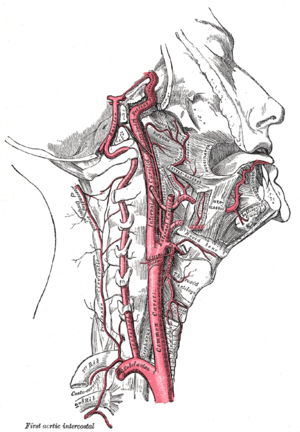

نبض أو نبض القلب Pulse هو الموجة المتولدة في الشرايين نتيجة لانقباض القلب وهو مايُدعى بالدارج بدقات القلب. بمكن إحساس النبض عبر تحسس الشرايين الكبيرة في جسم الإنسان في مناطق قربها من سطح جسم الإنسان مثل العنق، والمعصم.

الرأس والعنق